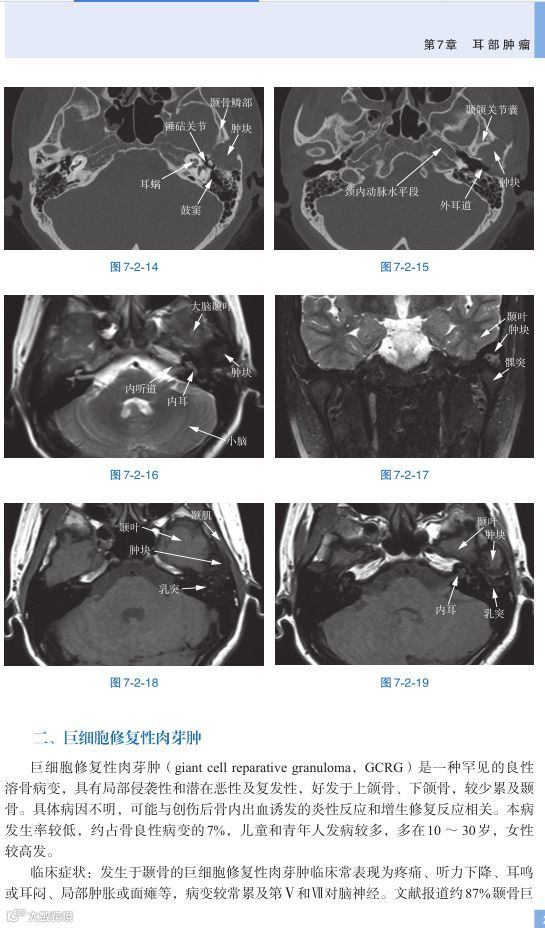

本书首先介绍耳部正常结构的影像学特点,从临床常用的CT和MRI检查出发,对水平位和冠状位的每个层面进行详细的描述,重点阐述了重要结构在不同层面的表现特征及其毗邻情况;进而以临床常见的耳科疾病典型病例为基础,结合疾病的临床特点、听力学检查及内镜所见,将重点放在阐述借助影像学检查和治疗耳科疾病的阅片特点上,包括中耳炎症、肿瘤、颅底疾病和内耳疾病等内容。

本书既有耳科的常见病和多发病,也介绍了许多罕见病。这些疾病的诊断是随着影像学技术的发展而被认识的,如半规管裂和听骨链畸形的诊断得益于薄层CT和CT的重建技术;内耳膜迷路积水的确诊是由于MRI内耳造影技术的改进;耳蜗神经缺损的诊断得益于MRI内听道斜矢状位的技术;MRI的T 1 加权3D FLAIR序列则可以观察到内耳膜迷路的出血现象。

耳部结构复杂精细使其影像学成为临床耳鼻喉专科医师掌握的一大难点。本书为我国著名的复旦大学附属眼耳鼻喉医院资深专家将十数年积累的临床资料汇集成的一本实用价值很高的原创著作。全书共分为7章,首先讲述耳部正常影像学,包括CT水平位和冠状位解剖结构;耳部、内听道水平位和冠状位MRI解剖结构及颞骨CT的多平面重建。在此基础上分别介绍和分析了耳和侧颅底多种疾病的影像学特点,包括畸形及外伤、中耳炎、中耳胆脂瘤、耳硬化症、内耳疾病、耳部肿瘤等与临床诊疗相关的内容。本书语言精练、资料难得、易于掌握,所收集精选的千余幅影像图片配合仔细的分析标注,不失为耳科影像学入门和临床借鉴的重要读本。